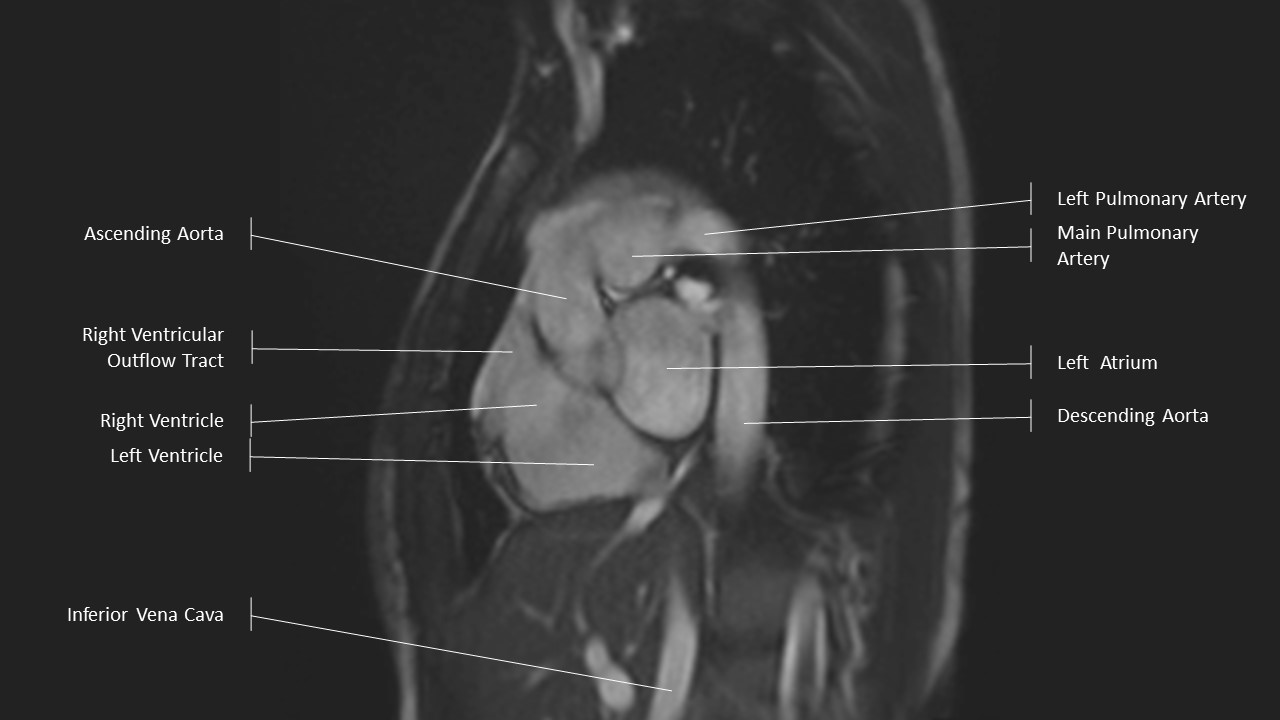

Aortic Arch Series